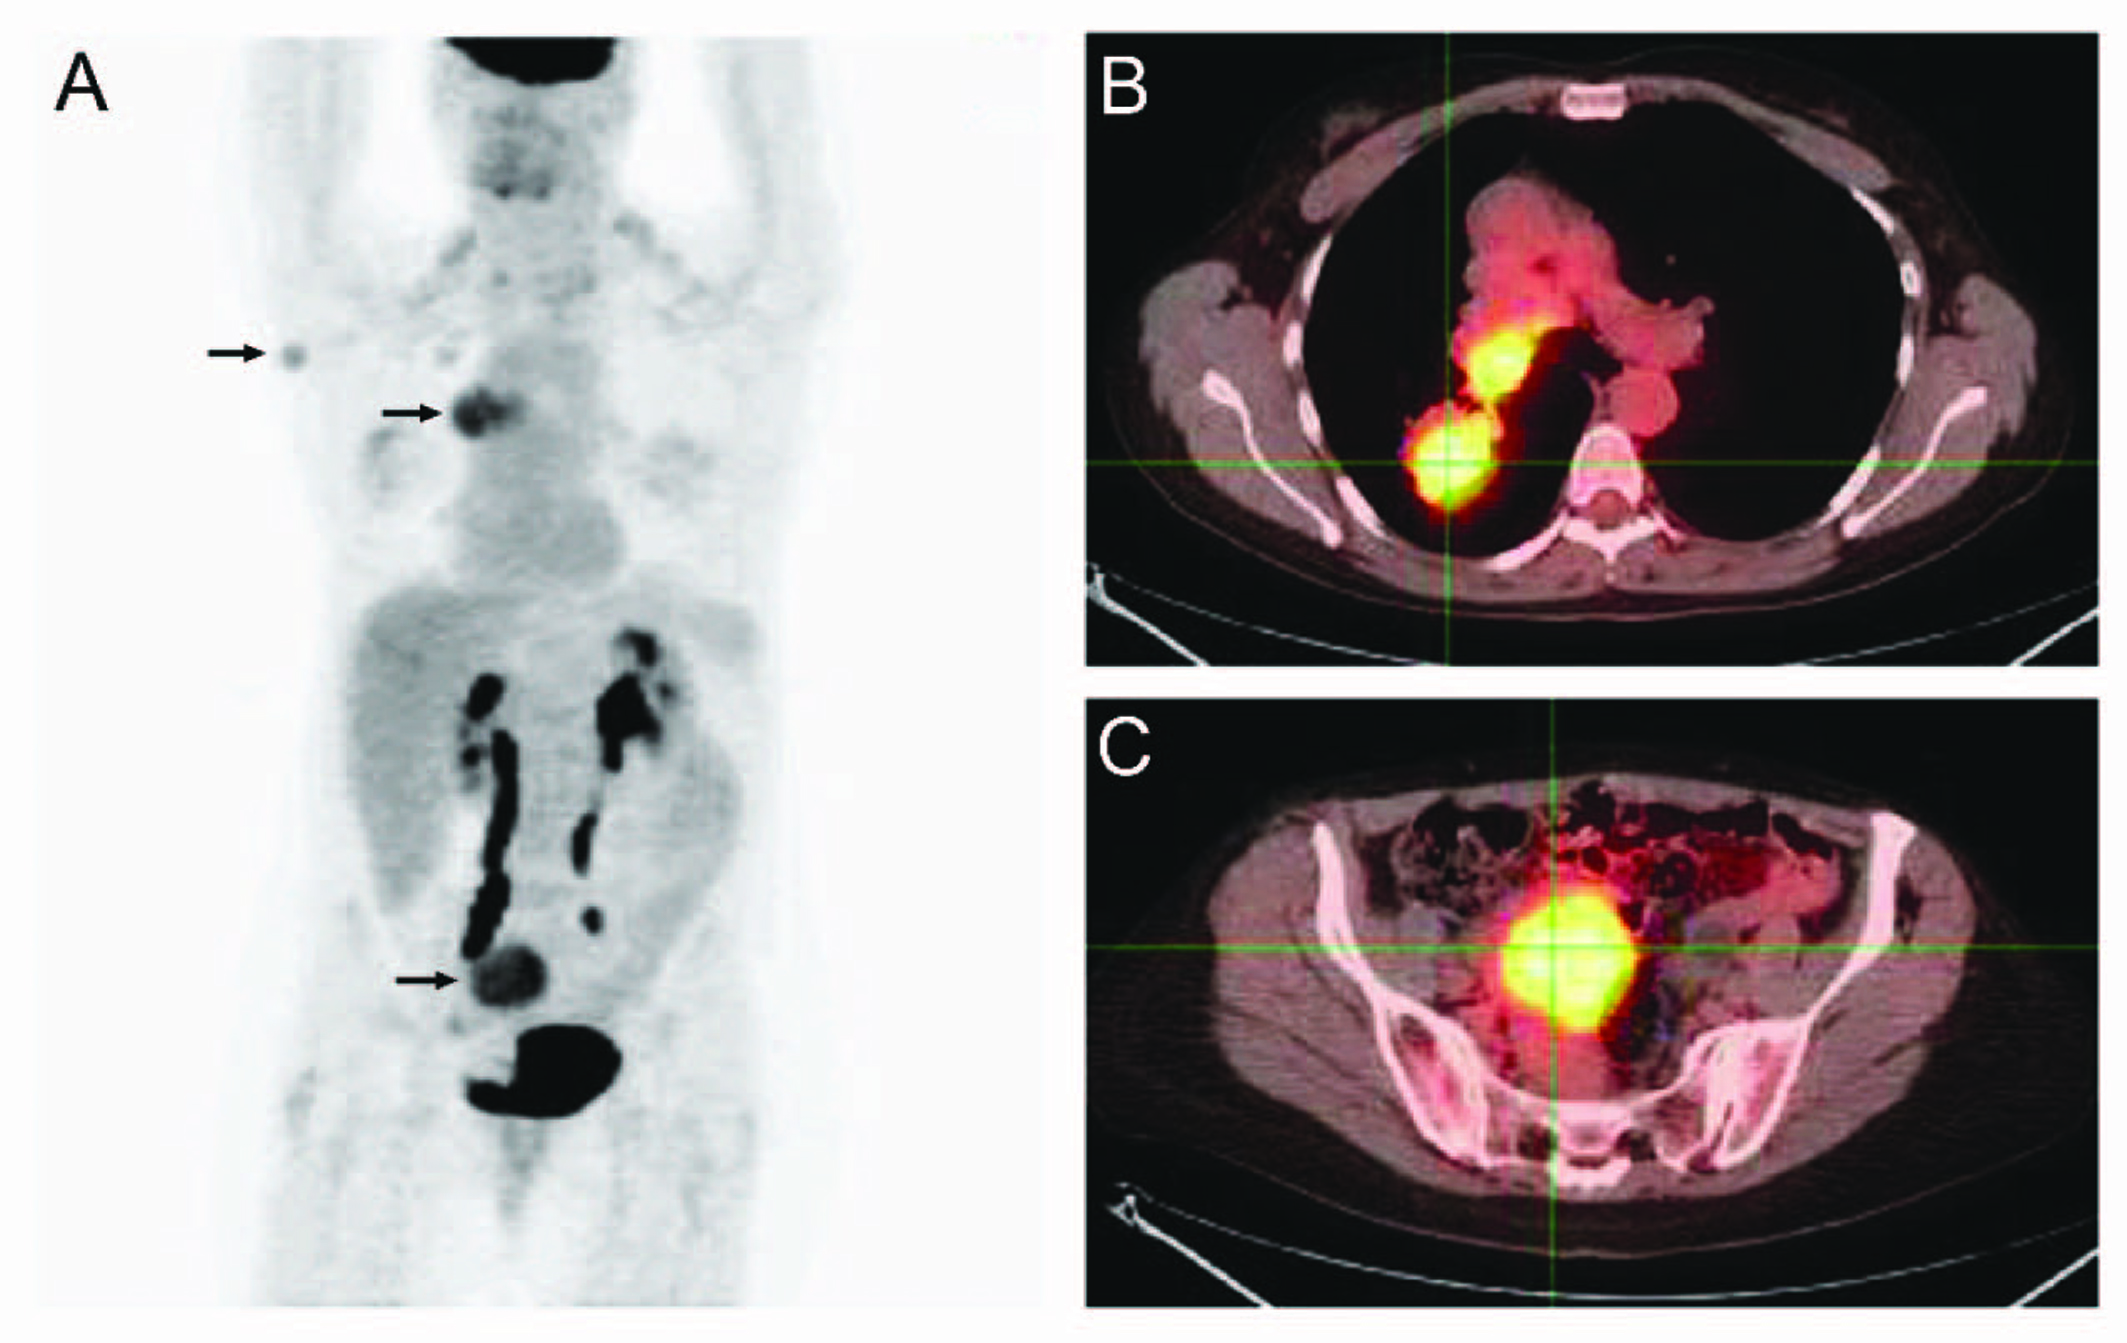

A 50-year-old woman presented with a single subcutaneous nodule in her right axilla. The patient first felt the nodule 1.5 years before, but ignored it as she thought it might be part of fibroadenomatous breast disease. The mass rapidly grew to 2.1 cm and became harder in the previous few months (Fig. 1). The patient otherwise felt well. She noted significant weight loss of 35 pounds during the same period which she contributed to voluntary diet and exercise and she felt more energetic after the weight loss. She had a 25-pack-year history of smoking. Multiple cancers were reported in the patient’s family members. Breast ultrasound and mammogram revealed bilateral benign-appearing cysts unchanged from those found in previous studies. Ultrasound showed high vascularity in the right axillary mass which was biopsied. Pathological examination demonstrated that the tumor consisted of fascicles of spindle cells with small areas of necrosis, mild cytologic atypia, and a low mitotic rate. Immunostaining showed strong positivity for chromogranin and synaptophysin and moderate positivity for TTF-1 (thyroid transcription factor-1), a lung marker (Fig. 2). Breast cancer markers were negative. Ki-67 labeling index was 5-10%. These findings were consistent with an intermediate-grade neuroendocrine carcinoma probably from the lungs. Chest CT showed two right hilar masses, measuring 4.3 x 3.5 cm and 3.1 x 2.9 cm, right hilar and pretracheal adenopathy, and a 1.8 cm right middle lobe solitary lung nodule. These lung masses were hypermetabolic on PET/CT which also revealed a 4.9 x 4.4 cm hypermetabolic mass in the pelvis and identified the right axiallary nodule as mildly hypermetabolic (Fig. 3). No liver metastasis was noted. Chromagranin A and neuron-specific enolase levels were normal. Pancreastatin levels were 192 pg/ml (10 - 135), ACTH 85 pg/ml (6 - 58), serotonin 234 ng/ml (22 - 180), and cortisol 17.8 mcg/dl (3 - 14). Octreotide scan failed to detect any foci. The patient was diagnosed with metastatic atypical lung carcinoid and chemotherapy was planned. Before initiating chemotherapy, she had a brief episode of altered mental status that was consistent with seizure. Brain MRI demonstrated a left temporal lobe metastasis which was surgically resected. Pathological examination of surgical samples revealed similar features to those in the subcutaneous nodule.

![]() Click for large image | Figure 3. PET/CT study: (A) Whole body PET; (B) PET/CT overlay of chest; (C) PET/CT overly of pelvis. Arrows: hypermetabolic foci on PET. |